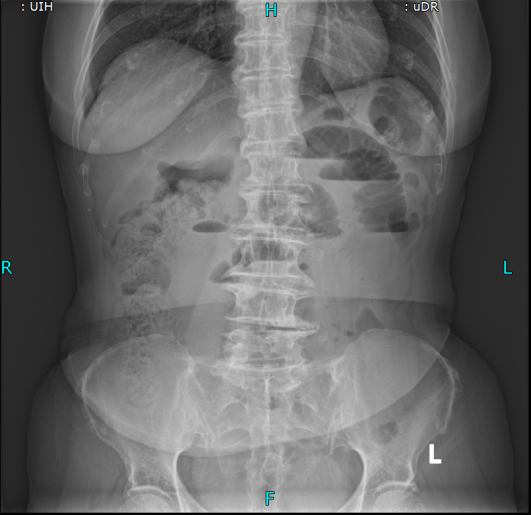

置入导管后肠梗阻明显减轻

考虑到王奶奶疼痛难忍、无法移动,普外科团队直接将胃镜设备推至病房床边,不到10分钟就完成了肠梗阻导管置入术。这根长达280cm的特殊导管不仅快速缓解了王奶奶的胀痛,还为后续治疗争取了关键时间,也为手术提供了安全保障。

肠梗阻导管置入后,王奶奶的腹痛腹胀明显缓解,叶晋生迅速启动多学科会诊(MDT),麻醉科、ICU、消化科等专家,综合评估王奶奶的高龄、高血压、既往手术史等多重风险,最终确定手术方案:腹腔镜下肠粘连松解术+小肠部分切除术。